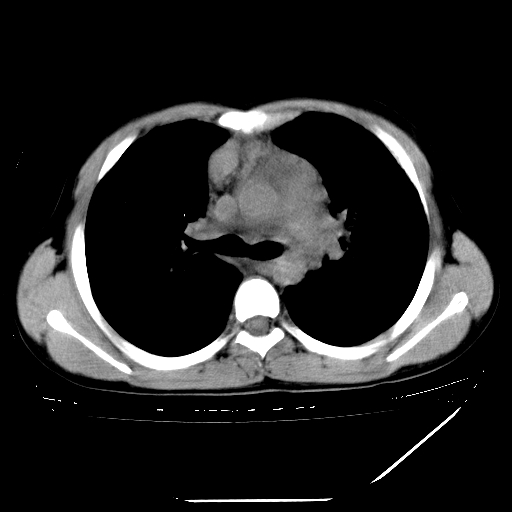

男,13岁,咳嗽、咳痰伴发热一周。

上纵隔课件多枚淋巴结,部分相互融合,左侧支气管壁增厚,肺纹理较右侧增粗,患者,男,13岁,

中上纵隔见多枚淋巴结肿大,部分相互融合成团片,左肺门增大,上叶支气管变窄,肺内多处斑片状 索条状及棉絮状致密影。临床“男,13岁,咳嗽、咳痰伴发热一周。”首先考虑:原发综合征!不除外淋巴瘤可能!

纵隔多发肿大淋巴结,部份有融合改变。双肺血管气管束增厚,以肺门为中心向外周散发,以左肺下叶为明显。考虑淋巴瘤可能性大。不除外原发综合征。

中上纵隔见多枚淋巴结肿大,部分相互融合成团片,左肺门增大,上叶支气管变窄,左肺支气管血管束增粗,可见磨玻璃样影。临床“男,13岁,咳嗽、咳痰伴发热一周。”首先考虑:淋巴瘤可能性大!

中上纵隔见多枚淋巴结肿大,部分相互融合成团片,纵隔内脂肪间隙模糊,左肺门增大,上叶支气管变窄,左肺支气管血管束增粗,可见磨玻璃样影。考虑纵隔淋巴管炎

单纯看片子感觉左侧肺通气不畅,而不像肺内病变引起的纵隔病变。而且纵隔及左肺门都有淋巴结增大。首先还是考虑一下结节病,不排除淋巴瘤!!!